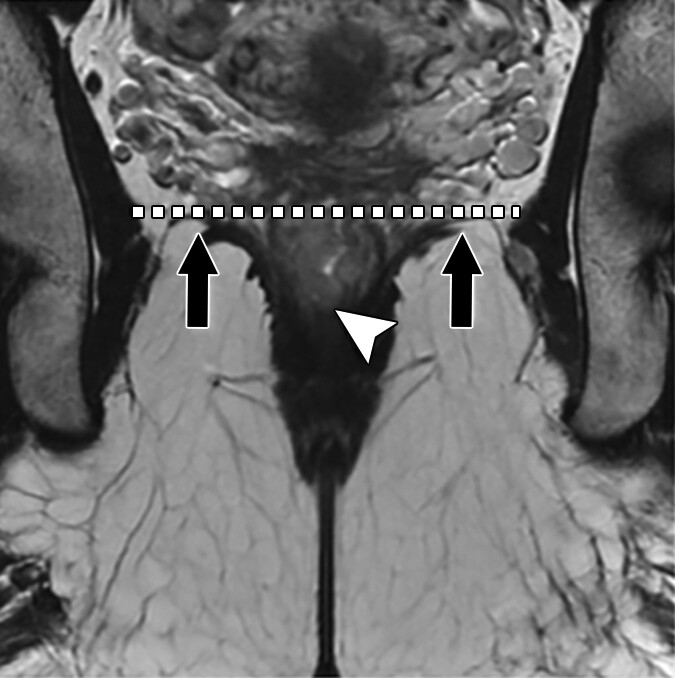

Epitransverse and paracondylar processes at the atlanto-occipital junction are easy to miss but can cause symptoms and complicate surgery. Learn what they look like and why they matter in this latest R3 case report. r3journal.org/doi/10.2214/r3…

Epitransverse and paracondylar processes at the atlanto-occipital junction are easy to miss but can cause symptoms and complicate surgery. Learn what they look like and why they matter in this latest R3 case report.